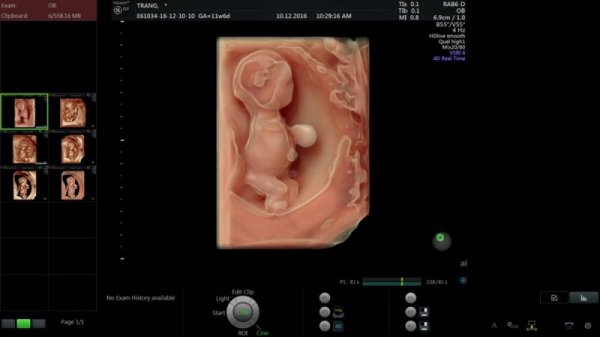

2.  Đi khám và siêu âm thai lần 2 (11 tuần – 13 tuần 6 ngày): Đo độ mờ da gáy

• Khám thai và tư vấn.

• Siêu âm đo độ mờ da gáy.

• Mẹ cần xét nghiệm Double test tầm soát dị tật của thai nhi.